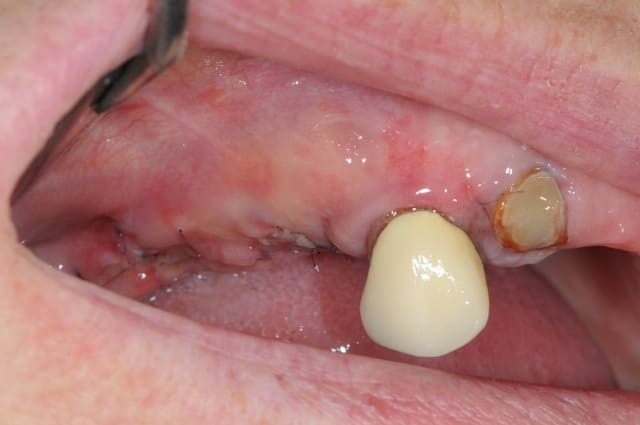

je poste ici les photos de ce matin pour la maman d'Aurélie.

du coup j'en fais profiter tous le monde...

14 était fracturée et il y avait une infection +++ au niveau de la 15 avec perte de la table vestibulaire.

j'ai mis du bioos et membrane collagène AT résorbable fixée par trois pins.

le port de la prothèse est contre-indiqué pendant 2 mois ou alors avec un sérieux évidement de l'intrados.

elle a eu le plus dure. la pose des implants plus tard,ça sera du gâteau.